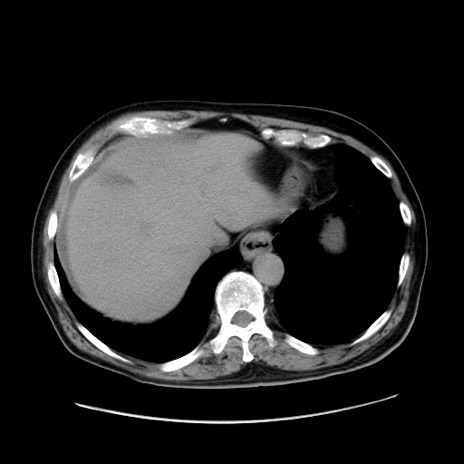

冠状断像